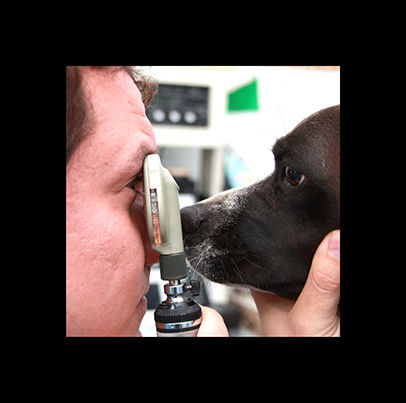

medicina general

En nuestra clinica recibimos a nuestros clientes, escuchamos sus explicaciones y junto con una exploración y ayudados de métodos complementarios nos acercamos a un diagnostico.